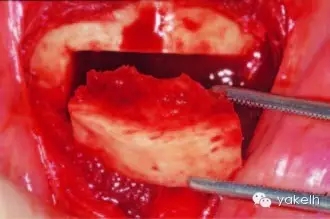

¤¤暴露頦部后,設(shè)計取骨的切口。取骨塊的大小由受區(qū)所需的骨量決定。骨切開處距離根尖以及頦孔最少應(yīng)有5mm。多數(shù)情況下,要保留下頜骨下緣以及舌側(cè)皮質(zhì)骨的完整性。唇側(cè)皮質(zhì)較厚,其內(nèi)側(cè)的松質(zhì)骨通常較致密??梢允褂脺u輪手機(jī)碳合金裂鉆(557號或701號)或者來復(fù)鋸將骨切開(圖13.19)。切透皮質(zhì)骨達(dá)松質(zhì)骨后,用骨鑿將骨塊移除(圖13.20)。用單面鑿沿著骨切開線輕輕敲擊,除了下頜骨下緣,將骨塊從基底部折斷。在中線處時,也可將塊狀骨分割成矩形骨塊,分段獲取。分成兩個骨塊后更容易獲取,因為可以用骨鑿將第二塊骨塊從舌側(cè)撬起。另外,移除塊狀骨后,還可使用骨刮匙、鑿子、咬骨鉗、環(huán)形鉆獲取

一些松質(zhì)骨,但是松質(zhì)骨的量十分有限。在移除塊狀骨后,可以將止血材料如膠原或明膠海綿置于松質(zhì)骨表面。當(dāng)獲取較大的骨塊時,供區(qū)應(yīng)使用骨替代材料如羥基磷灰石,來維持唇側(cè)的外形(圖13.21)。較少或者顆粒狀的骨移植時,可使用環(huán)形鉆、骨收集器、骨挖器來獲取。把骨塊植入受區(qū)后,再將供區(qū)的傷口縫合,這可以縮短取骨與植骨之間的時間。分離前庭溝切口上方的黏膜,以減少水腫和下唇運動所產(chǎn)生的張力。用可吸收縫線分層縫合前庭溝切口(圖13.22)。深層組織使用4-0可吸收線縫合,表層黏膜使用4-0鈷腸線縫合。術(shù)后使用壓力繃帶包扎頦部,以減少水腫、血腫形成及切口裂開(圖13.23)。

圖13.20 從頦部獲取厚的皮髓質(zhì)骨塊。